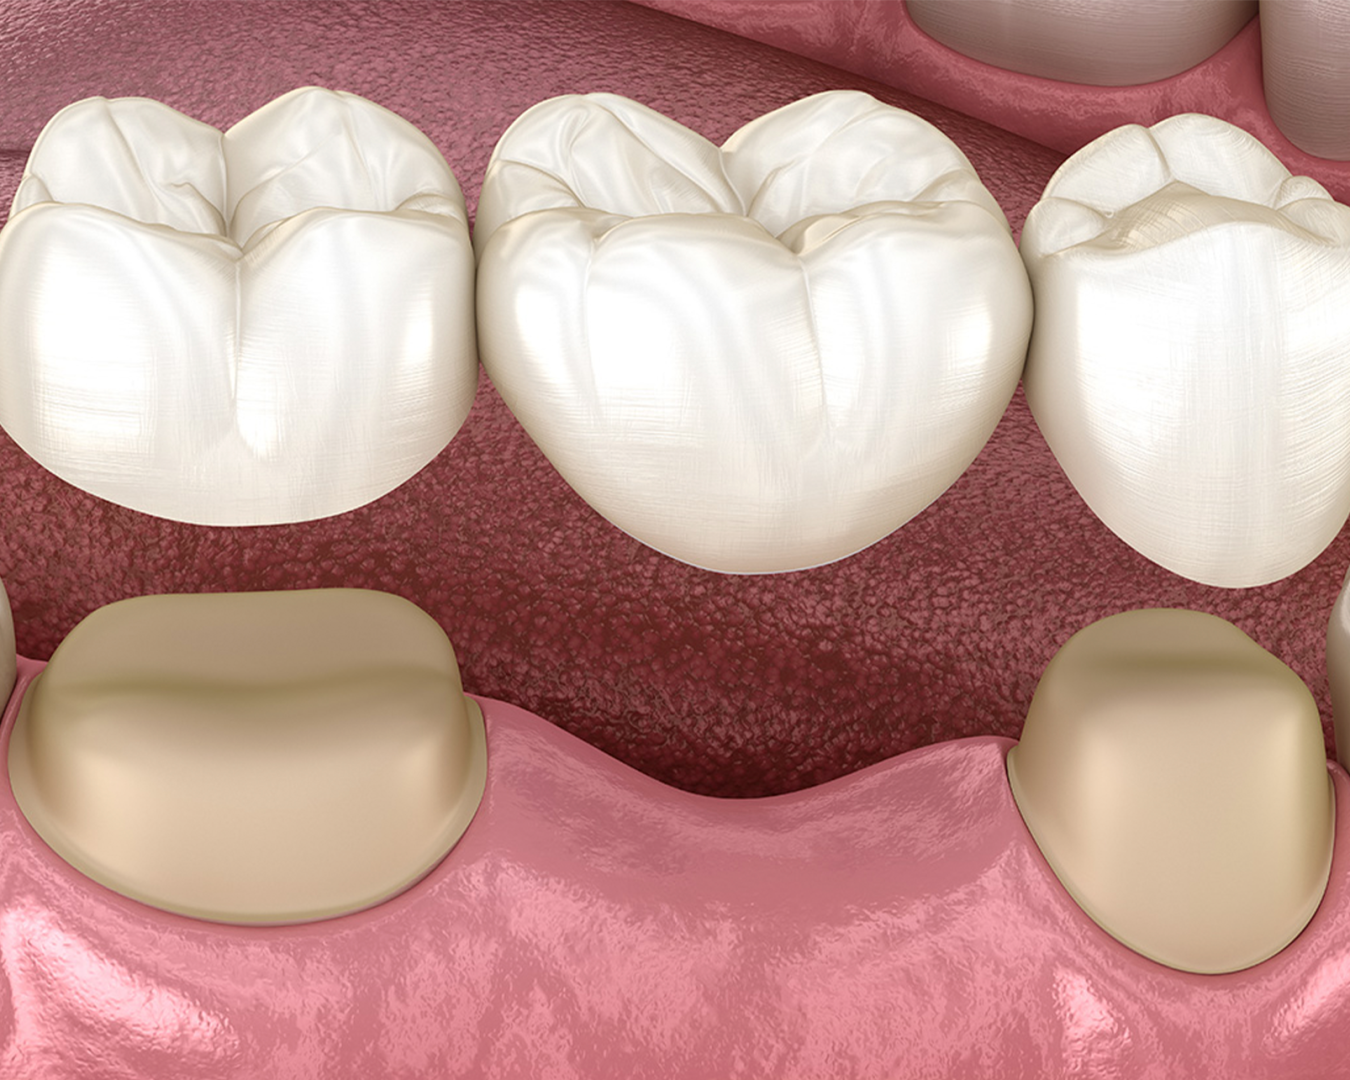

Prótesis Fija

Las prótesis dentales reemplazan dientes perdidos y ayudan a recuperar la función y la estética.